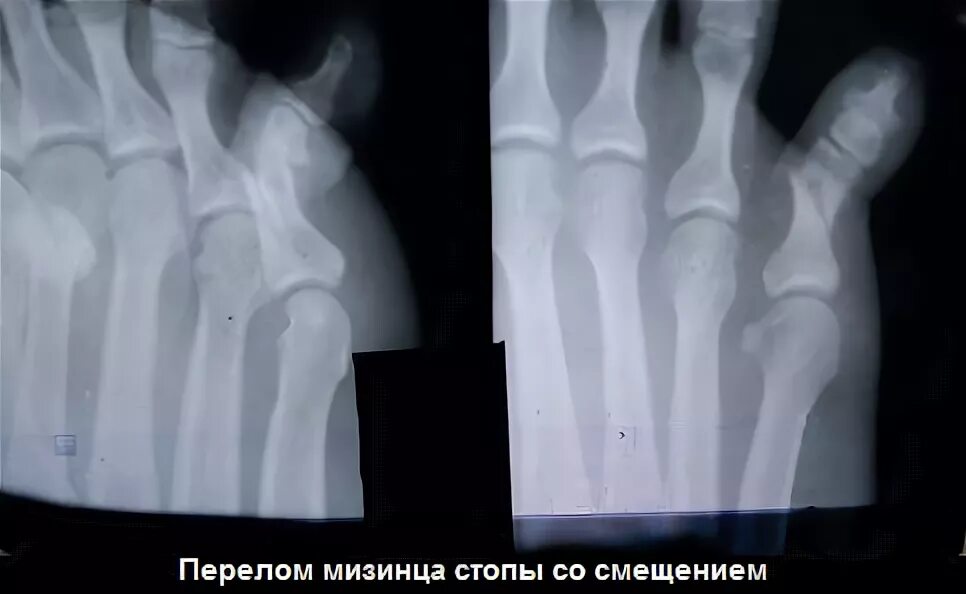

Сколько срастается перелом мизинца